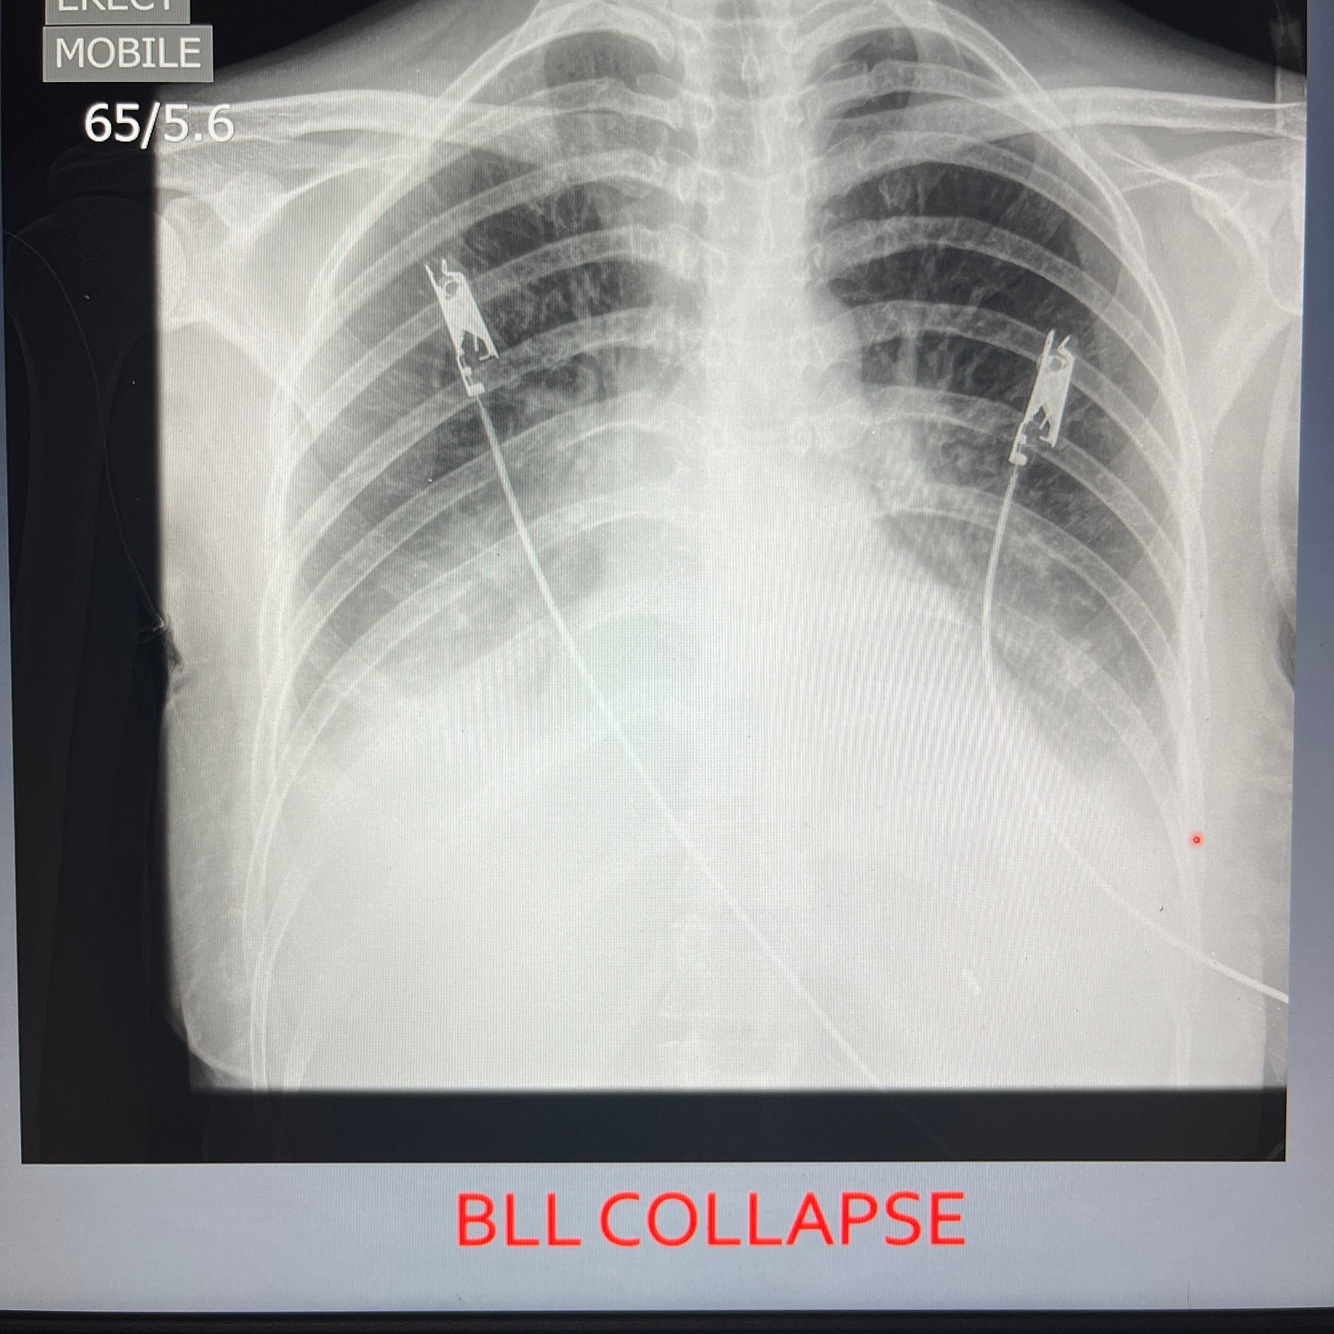

What are the direct signs of lobar collapse ?

Fissures displaces

Opacification of collapsed lobe due to loss of air

What are the indirect signs of a collapsed lobe on CXR?

Hilum displaced

Mediastinal shift towards collapsed side

Loss of vol in ipsilateral hemithorax

Ipsilateral diaphragm elevation

Crowding of ribs

Compensatory hyperlucency

Silhouette of diaphragm or heart boarder